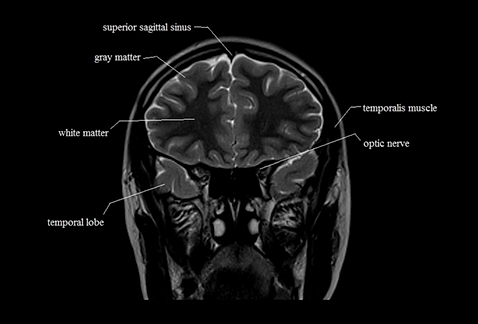

This is the coronal brain. In this slice, 13 parts of the brain are visualized. Can you identify the missing part in this slice ?